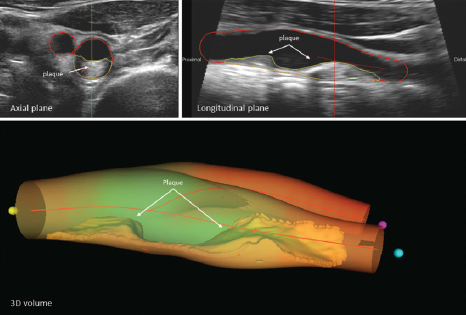

(bottom) provides a detailed and accurate visualization of the plaque, allowing a thorough assessment of the disease.

The study included 5,716 asymptomatic U.S. adults with an average age of 69 years (56.7% women) who were examined from 2008 to 2009. The study participants were examined with two imaging techniques. Atherosclerotic plaques in the carotid arteries were measured with vascular ultrasound, which allows detailed visualization of the interior of blood vessels, and calcification of the coronary arteries was assessed by computed tomography.

“Vascular ultrasound is a non-invasive and affordable test, and the valuable prognostic information it provides can be used to improve risk stratification and to target lifestyle recommendations for the control of cardiovascular risk factors,” explains Borja Ibáñez, PhD, Scientific Director of the CNIC.